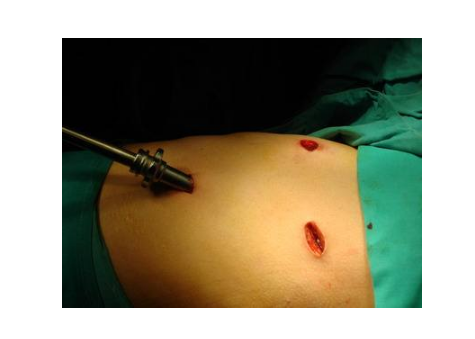

漏斗胸圖片

A:小兒漏斗胸的治療主要是以手術治療方式為主,臨床上可分為傳統手術方法以及微創矯形手術。傳統的手術包括胸骨翻轉術以及胸肋抬舉術兩種, 但是對於傳統手術,對孩子的創傷比較大。所以臨床上,目前採用微創漏斗胸矯形手術的方式比較多,是將塑形好的合金鋼板……